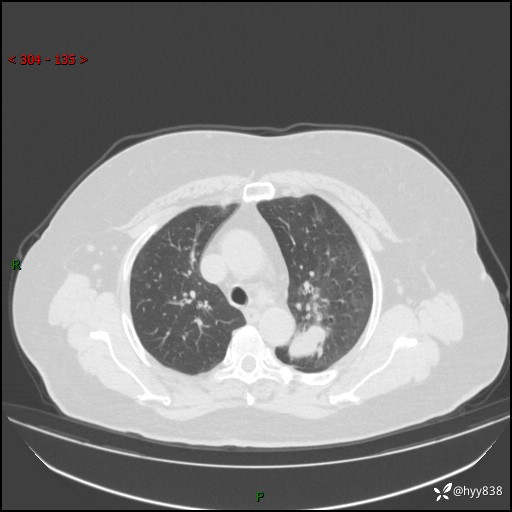

老年女性,左上肺结节8年。典型又不典型,看你如何解读---结果公布(值得分析)

主诉:检查发现左上肺结节8年,较前增大。

简要病史:患者于8年前体检行胸部CT检查发现左上肺结节(4mm),患者平素间断咳嗽咳痰,无心慌、胸闷、胸痛、呼吸困难、低热、盗汗,无头痛、头晕,无腹痛、腹胀等不适,未行特殊处理,定期复查。2023-09-21胸部CT示左上肺结节(2cm)较前增大,2024-02-01胸部CT示左上肺尖后段(39*32mm),左侧肺门及纵隔淋巴结增大,现患者欲求手术治疗,遂来我院就诊,以“左上肺结节”收入我科。 患者自起病以来,精神可,睡眠可,饮食可,大小便正常,体重无明显改变。

辅助检查:CT

胸部CT平扫